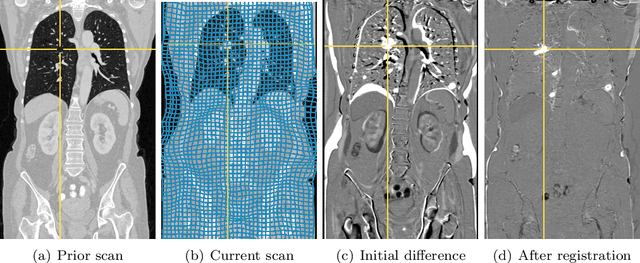

Abstract:We present a novel computational approach to fast and memory-efficient deformable image registration. In the variational registration model, the computation of the objective function derivatives is the computationally most expensive operation, both in terms of runtime and memory requirements. In order to target this bottleneck, we analyze the matrix structure of gradient and Hessian computations for the case of the normalized gradient fields distance measure and curvature regularization. Based on this analysis, we derive equivalent matrix-free closed-form expressions for derivative computations, eliminating the need for storing intermediate results and the costs of sparse matrix arithmetic. This has further benefits: (1) matrix computations can be fully parallelized, (2) memory complexity for derivative computation is reduced from linear to constant, and (3) overall computation times are substantially reduced. In comparison with an optimized matrix-based reference implementation, the CPU implementation achieves speedup factors between 3.1 and 9.7, and we are able to handle substantially higher resolutions. Using a GPU implementation, we achieve an additional speedup factor of up to 9.2. Furthermore, we evaluated the approach on real-world medical datasets. On ten publicly available lung CT images from the DIR-Lab 4DCT dataset, we achieve the best mean landmark error of 0.93 mm compared to other submissions on the DIR-Lab website, with an average runtime of only 9.23 s. Complete non-rigid registration of full-size 3D thorax-abdomen CT volumes from oncological follow-up is achieved in 12.6 s. The experimental results show that the proposed matrix-free algorithm enables the use of variational registration models also in applications which were previously impractical due to memory or runtime restrictions.